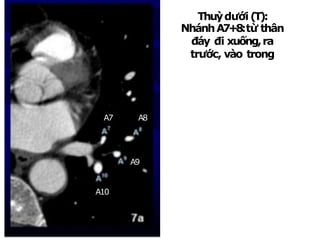

Thuỳdưới(T):

NhánhA7+8:từ thân

đáy đi xuống,ra

trước, vào trong

NhánhA9:rangoài

NhánhA10:rasau